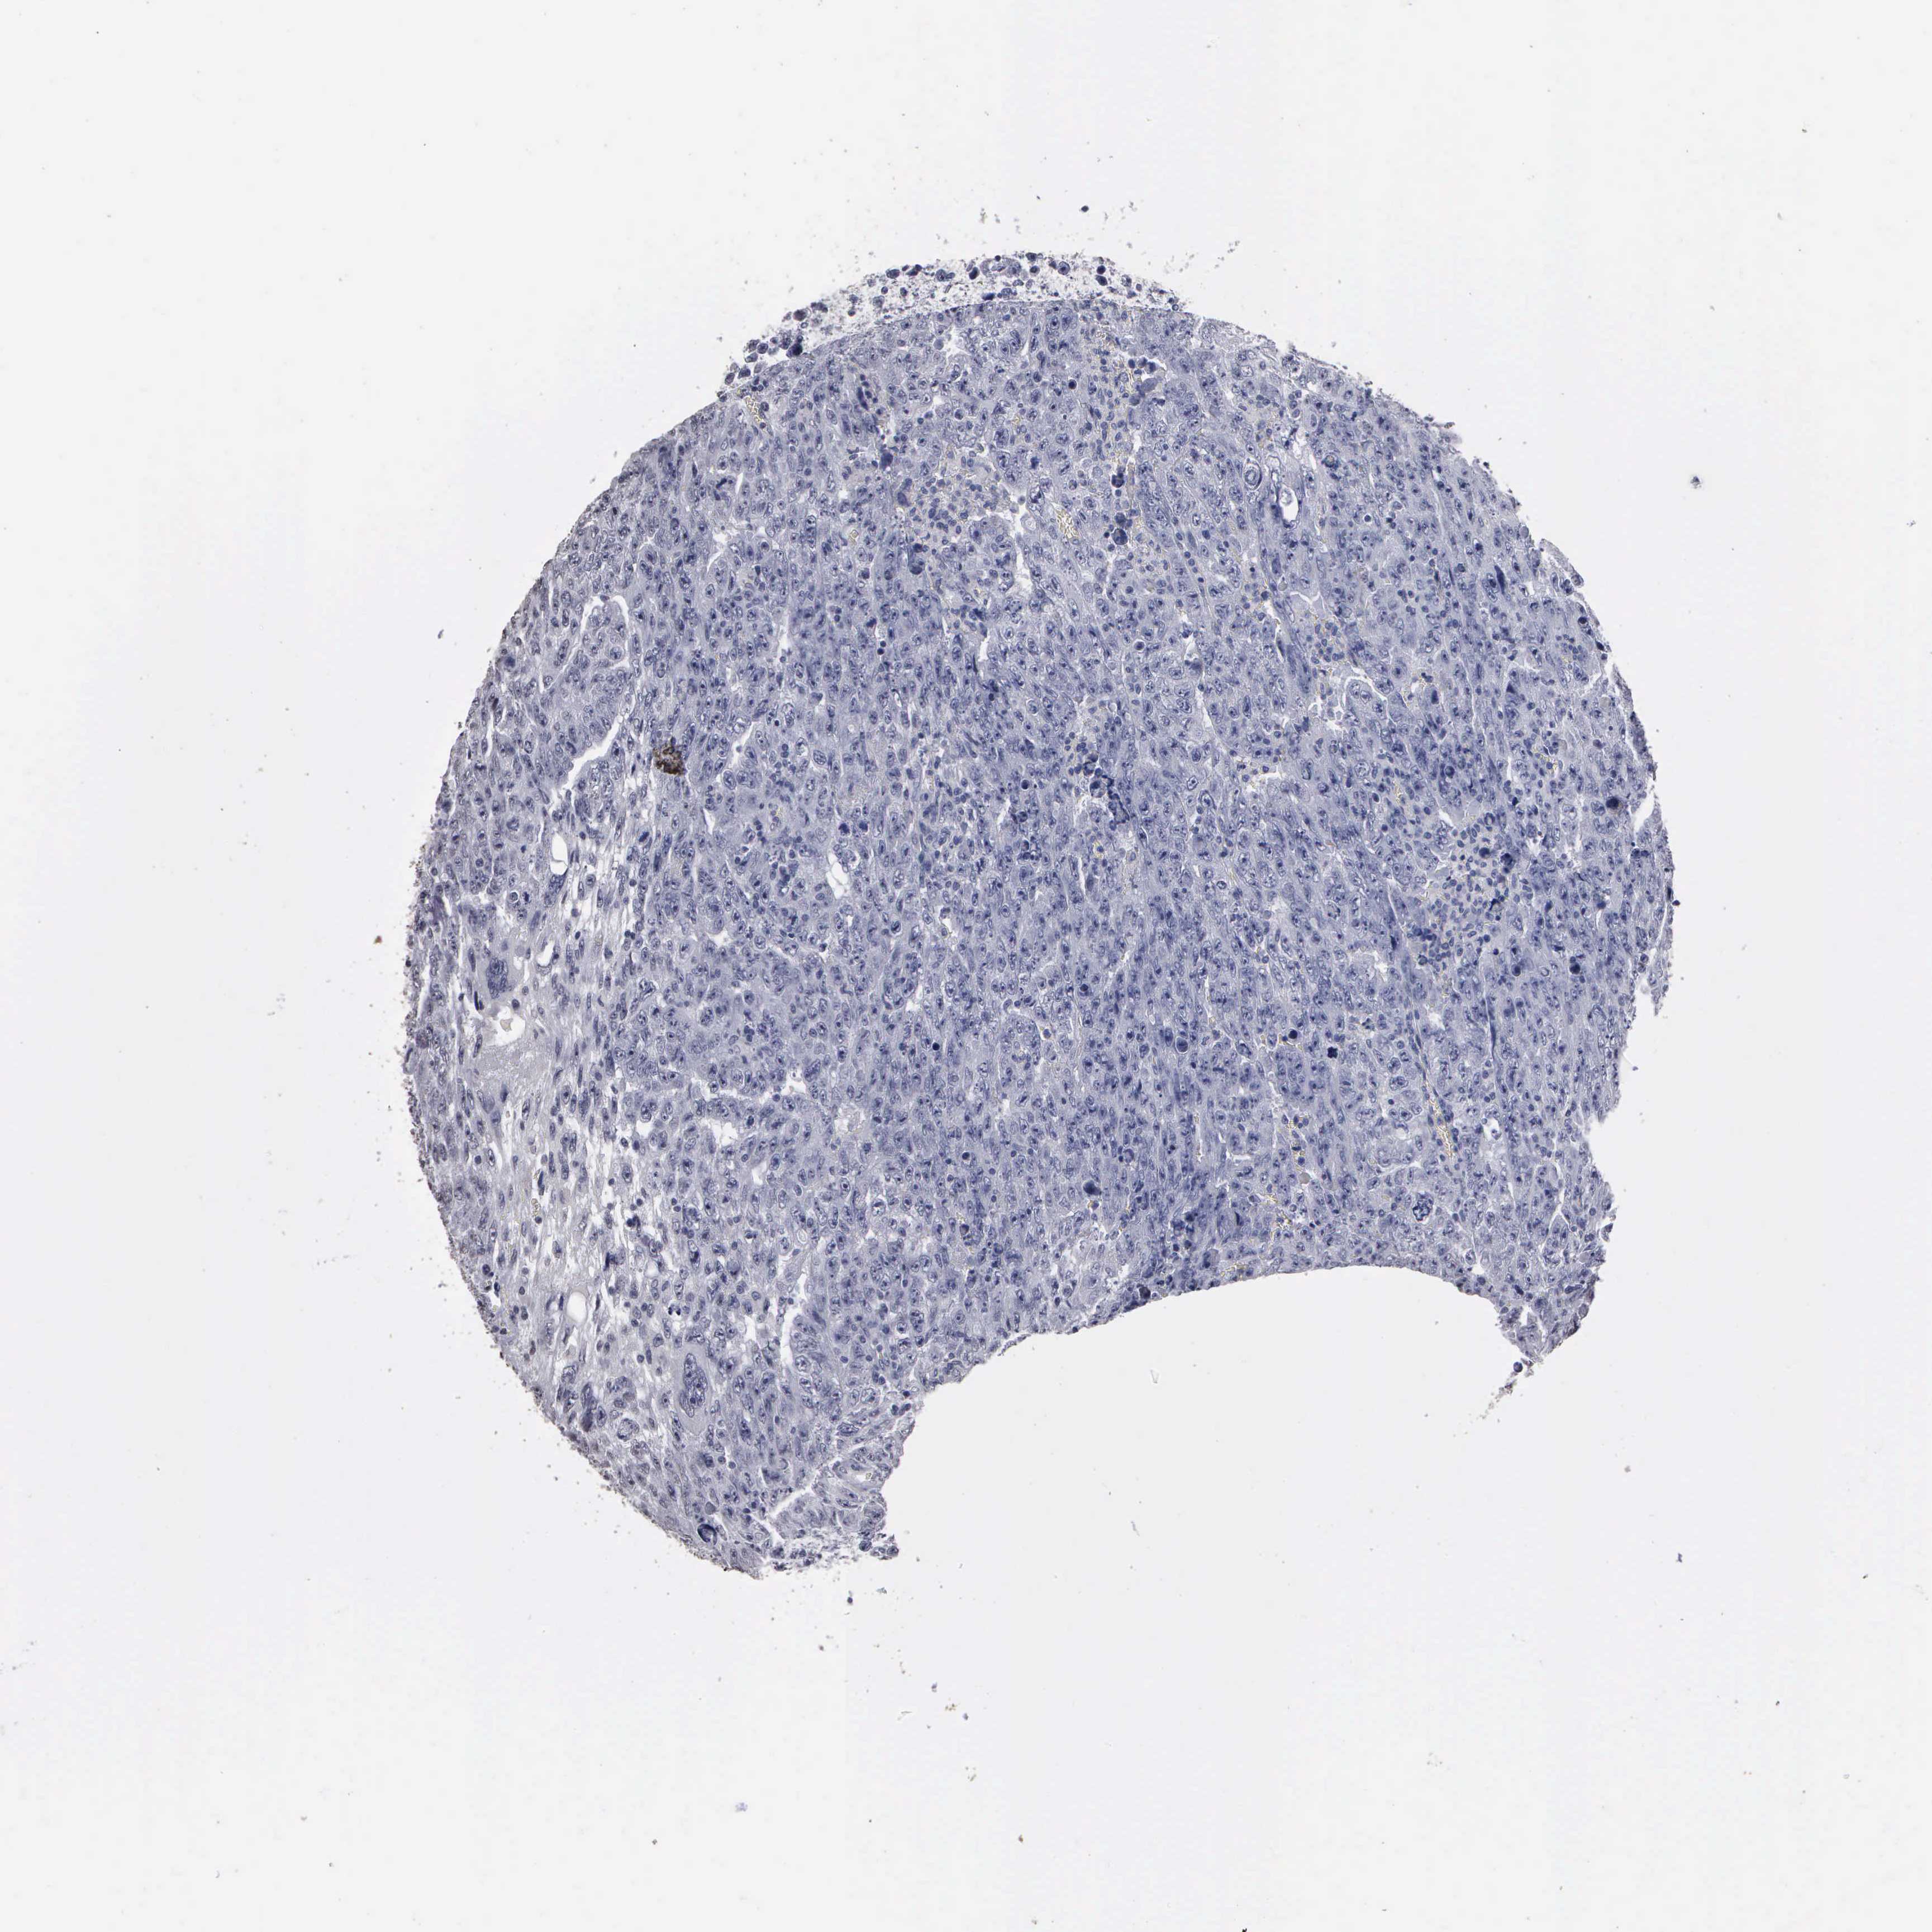

TESTIS CANCER - Protein expressioni

A mouse-over function shows sample information and annotation data. Click on an image to view it in a full screen mode. Samples can be filtered based on level of antibody staining by selecting one or several of the following categories: high, medium, low and not detected. The assay and annotation is described here.

Note that samples used for immunohistochemistry by the Human Protein Atlas do not correspond to samples in the TCGA dataset.

Antibody stainingi

Antibody staining in the annotated cell types in the current human tissue is reported as not detected, low, medium, or high, based on conventional immunohistochemistry profiling in selected tissues. This score is based on the combination of the staining intensity and fraction of stained cells.

Each image is clickable and will lead to virtual microscopy that enables deeper exploration of all samples and also displays staining intensity scores, fraction scores and subcellular localization as well as patient and tissue information for each sample.

Antibody HPA000728

Seminoma, NOS

Carcinoma, Embryonal, NOS